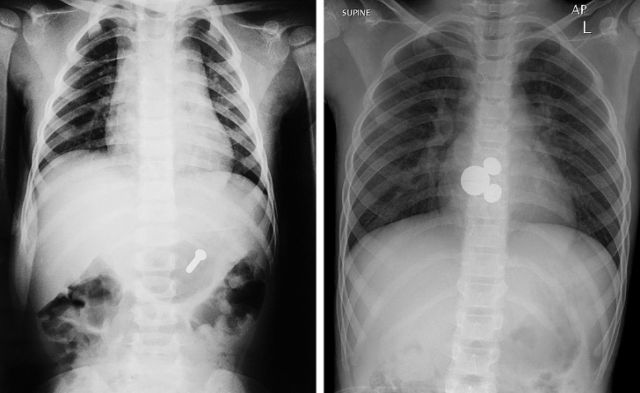

这就是为什么你不应该让孩子们玩小东西的原因。